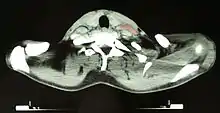

بعد تشخيص داء هودجكين، سيتم تحديد المرحلة لدى المريض؛ سيقومون بمجموعة متسلسة من الفحوصات والإجراءات التي ستحدد أي المناطق من الجسد المصابة بالمرض، هذه الإجراءات تضمن توثيق الجانب النسيجي والفحص الجسدي، واختبارات الدم، وصور أشعة إكس للصدر، وتَصْويرٌ مَقْطَعِيٌّ مُحَوسَب (CT) ،والتَّصْويرُ المَقْطِعِيُّ بالإِصْدارِ البُوزِيتْرُونِيّ( PET) ،والتَّصْويرُ بالرَّنينِ المِغْناطيسِيّ (MRI ) لمنطقة الصدر والبطن والحوض، وغالبا خزعة من نخاع العظم. التَّصْويرُ المَقْطِعِيُّ بالإِصْدارِ البُوزِيتْرُونِيّ الآن يستخدم بدلا من التصوير باستخدام عنصر الغاليُوم لتحديد المرحلة. عند استخدام التَّصْويرُ المَقْطِعِيُّ بالإِصْدارِ البُوزِيتْرُونِيّ، تظهر الأماكن المصابة بالليمفومة مضاءة بشكل ساطع ؛مما يوفر صور دقيقة ووقابلة للتكرار.[16] في الماضي، كان الأطباء يقومون بصورَةُ الأَوعِيَةِ اللِّمْفِيَّة وفَتْحُ البَطْن جراحيا ( والتي تضمن فتح البطن والتفحص بالنظر لوجود أي أورام ) . صور الأوعية الليمفية وفتح البطن جراحيا نادرا ما تعمل، وحل محلها الطرق المتطورة في التصوير، مثل تَصْويرٌ مَقْطَعِيٌّ مُحَوسَب (CT)، والتَّصْويرُ المَقْطِعِيُّ بالإِصْدارِ البُوزِيتْرُونِيّ ( PET).

يجب التميز بين ليمفومة هودجكين من انتفاخات العقد الليمفاوية غير السرطانية ( مثل العدوى) وأيضا من أنواع أخرى من السرطانات. التشخيص القطعي يكون بأخذ عينة من الورم في العقدة الليمفاوية نفسها ( مثل استئصال عينة وإجراء فحوصات باستخدام الميكروسكوب). فحوصات الدم أيضا تعمل ليتم التحقق من وظائف بعض الأعضاء الرئيسية ولتحديد ما إذا كان العلاج الكيماوي سيكون آمنا أم لا. التصويرالمقطعي بالإصدارالبوزيتروني تم عمله لاكتشاف أي ترسبات صغيرة لا يمكن أن تظهر باستخدام التصوير الطبقي (CT) . التصويرالمقطعي بالإصدارالبوزيتروني أيضا، يفيد في تحديد الوظائف (باستخدام جزيئات الجلوكوز المشعة لمعرفة الأنسجة الأكثر نشاطا حيويا). في بعض الأحيان يستخدم التصوير باستخدام الغاليوم بدلا من التصويرالمقطعي بالإصدارالبوزيتروني.